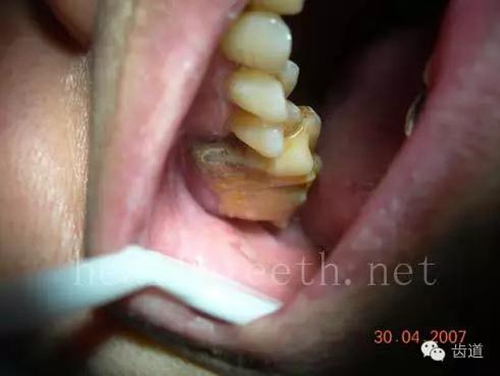

不良的根管充填治療

77.jpg

78.jpg

79.jpg